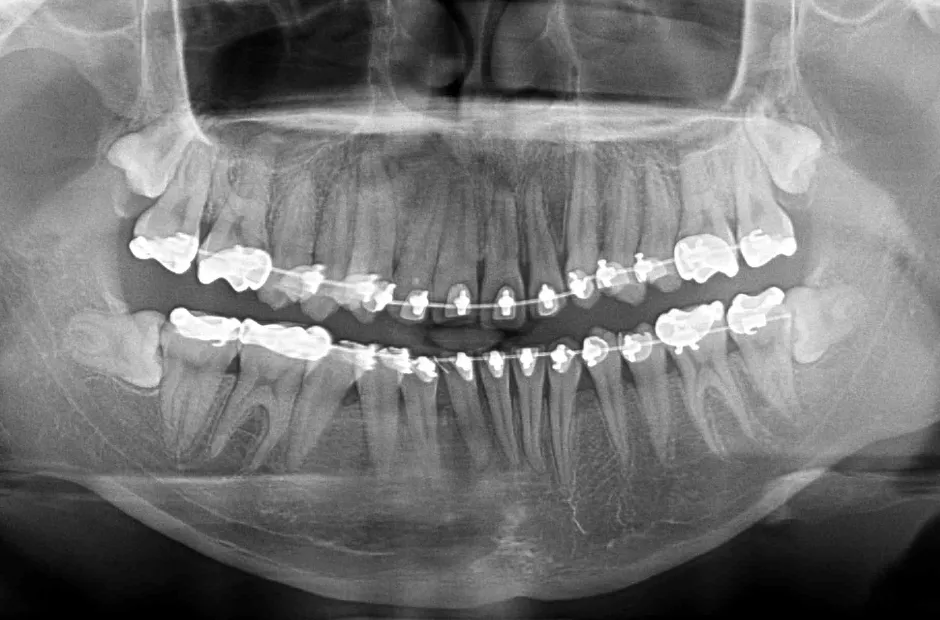

| 診断名・主訴 | 下顎前突、叢生 |

|---|---|

| 年齢・性別 | 23歳・女性 |

| 治療期間・回数 | 3年 |

| 治療に用いた主な装置 | 上顎5,5 下顎4,4 |

| 抜歯部位 | 舌側矯正 |

| 治療費 | 100万円(税抜) |

| リスク・副作用 | 装置による違和感・疼痛・歯肉退縮・歯根吸収・虫歯のリスクなど |

治療中